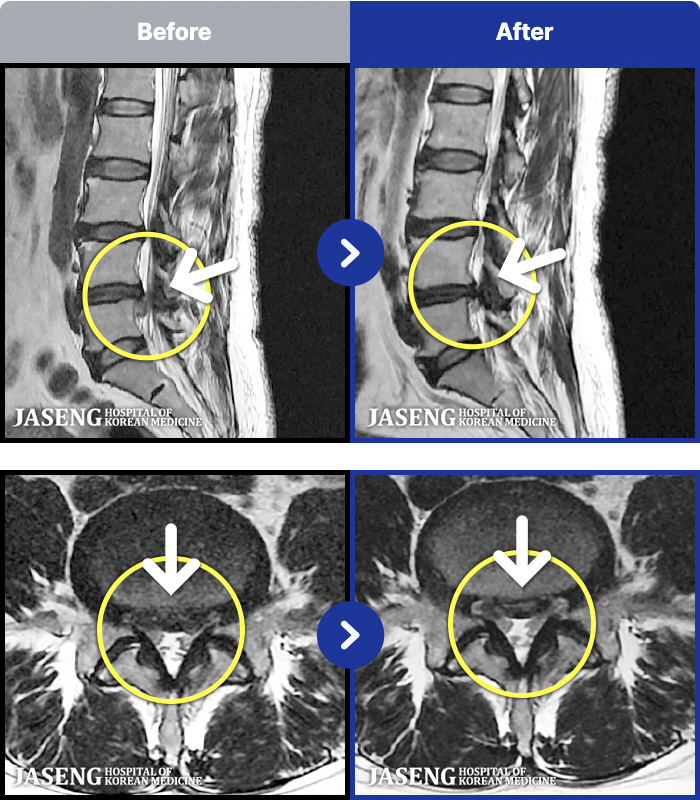

1,257 MRI ũ ʸ Ȯϼ.